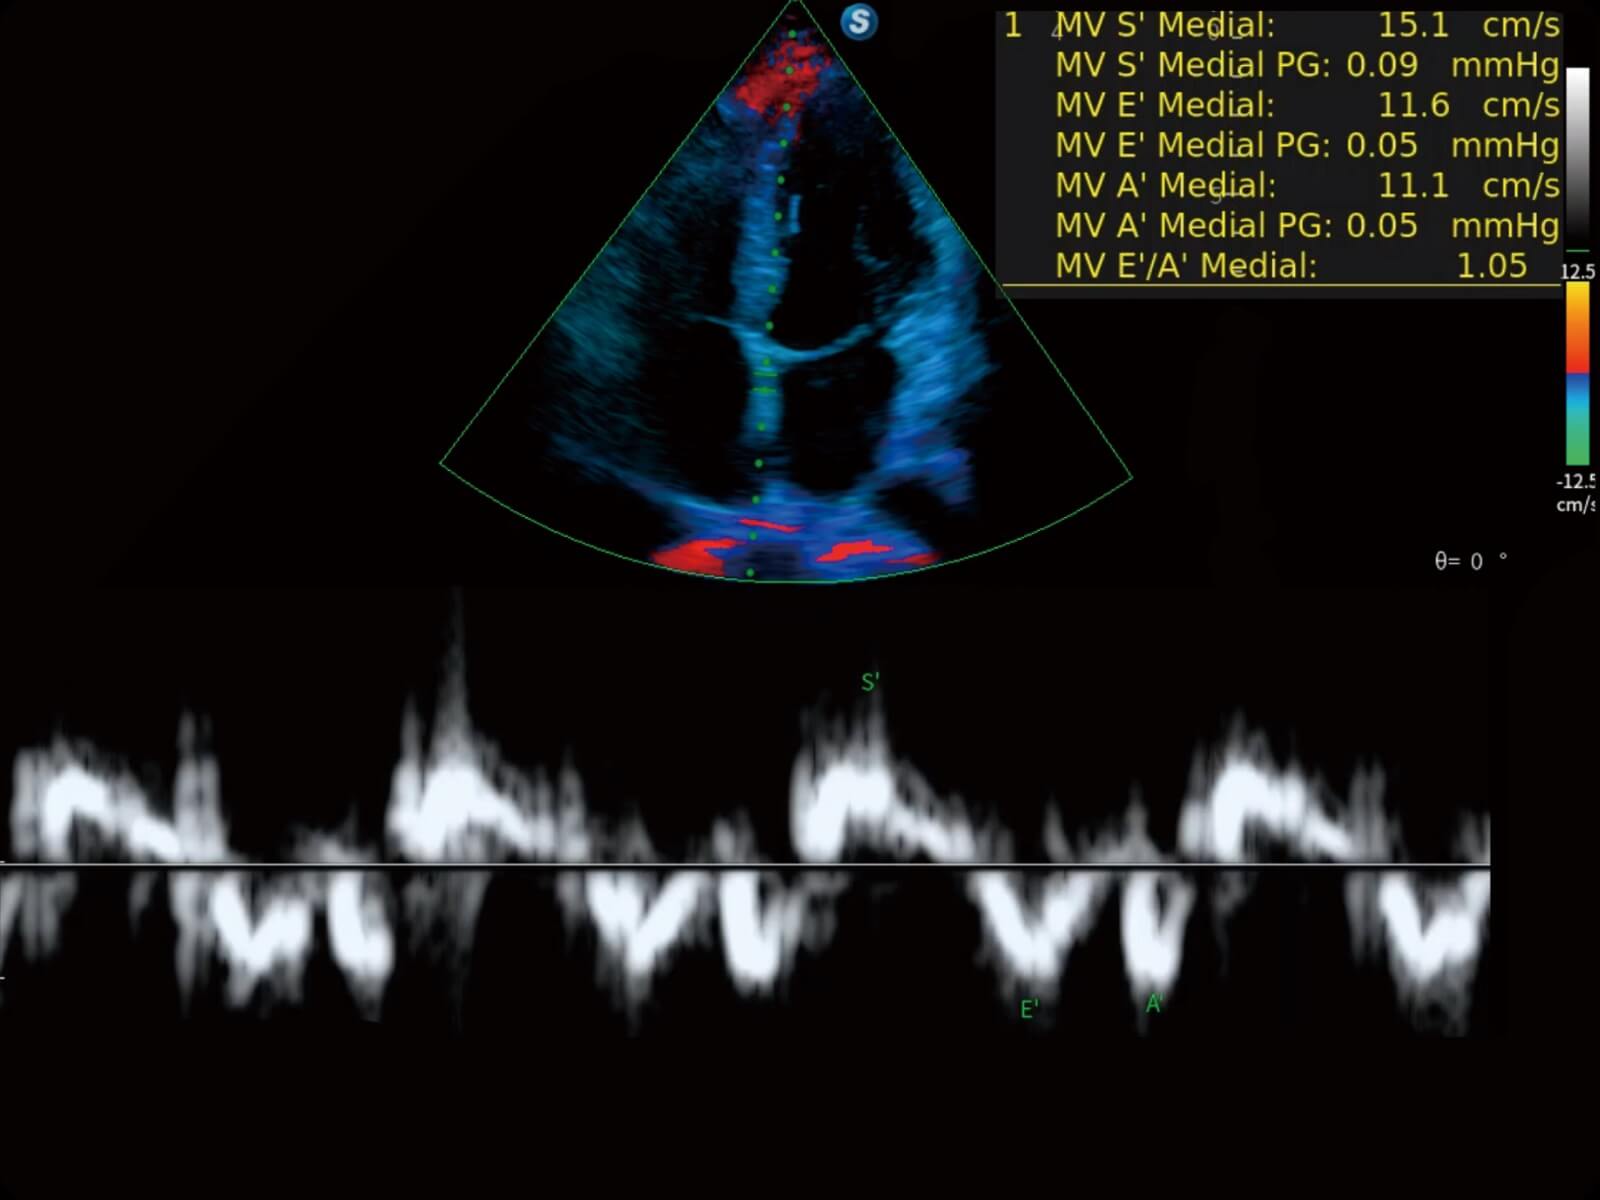

心脏应用